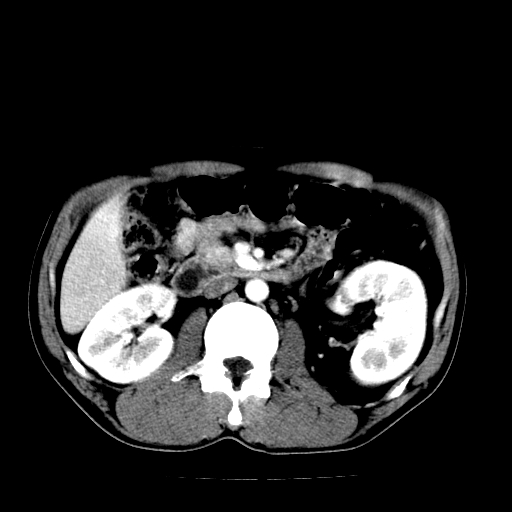

以下是引用天南地北在2007-4-30 13:36:00的发言:[br]支持慢性胰腺炎伴有假性囊肿

以下是引用andymaomao在2007-4-30 14:28:00的发言:[br]支持:1.慢性胰腺炎并假性囊肿形成可能;[br] 2.左肾形态稍增大,旋转不良。